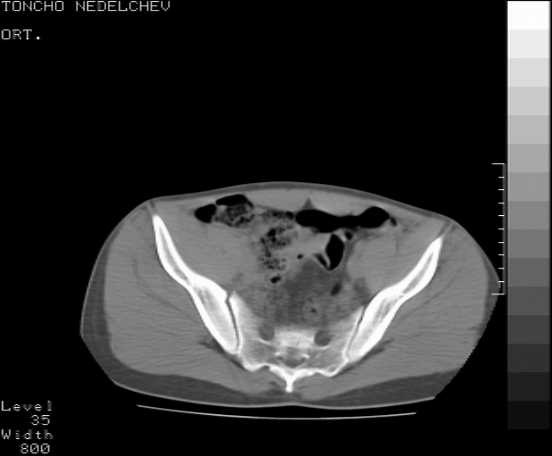

The details of the fracture are not so clear from the images sent...would you be able to send along an AP and Judet images as well as some additional axial images above and below the joint?

I’m not so sure that your patient has a Tr+PW pattern based on the images sent...maybe the fracture’s exact name won’t matter in the long run, but it’d be great to see enough images to make an accurate comment.

Here are some more axial images. What is your opinion as for the timing of the operative treatment?